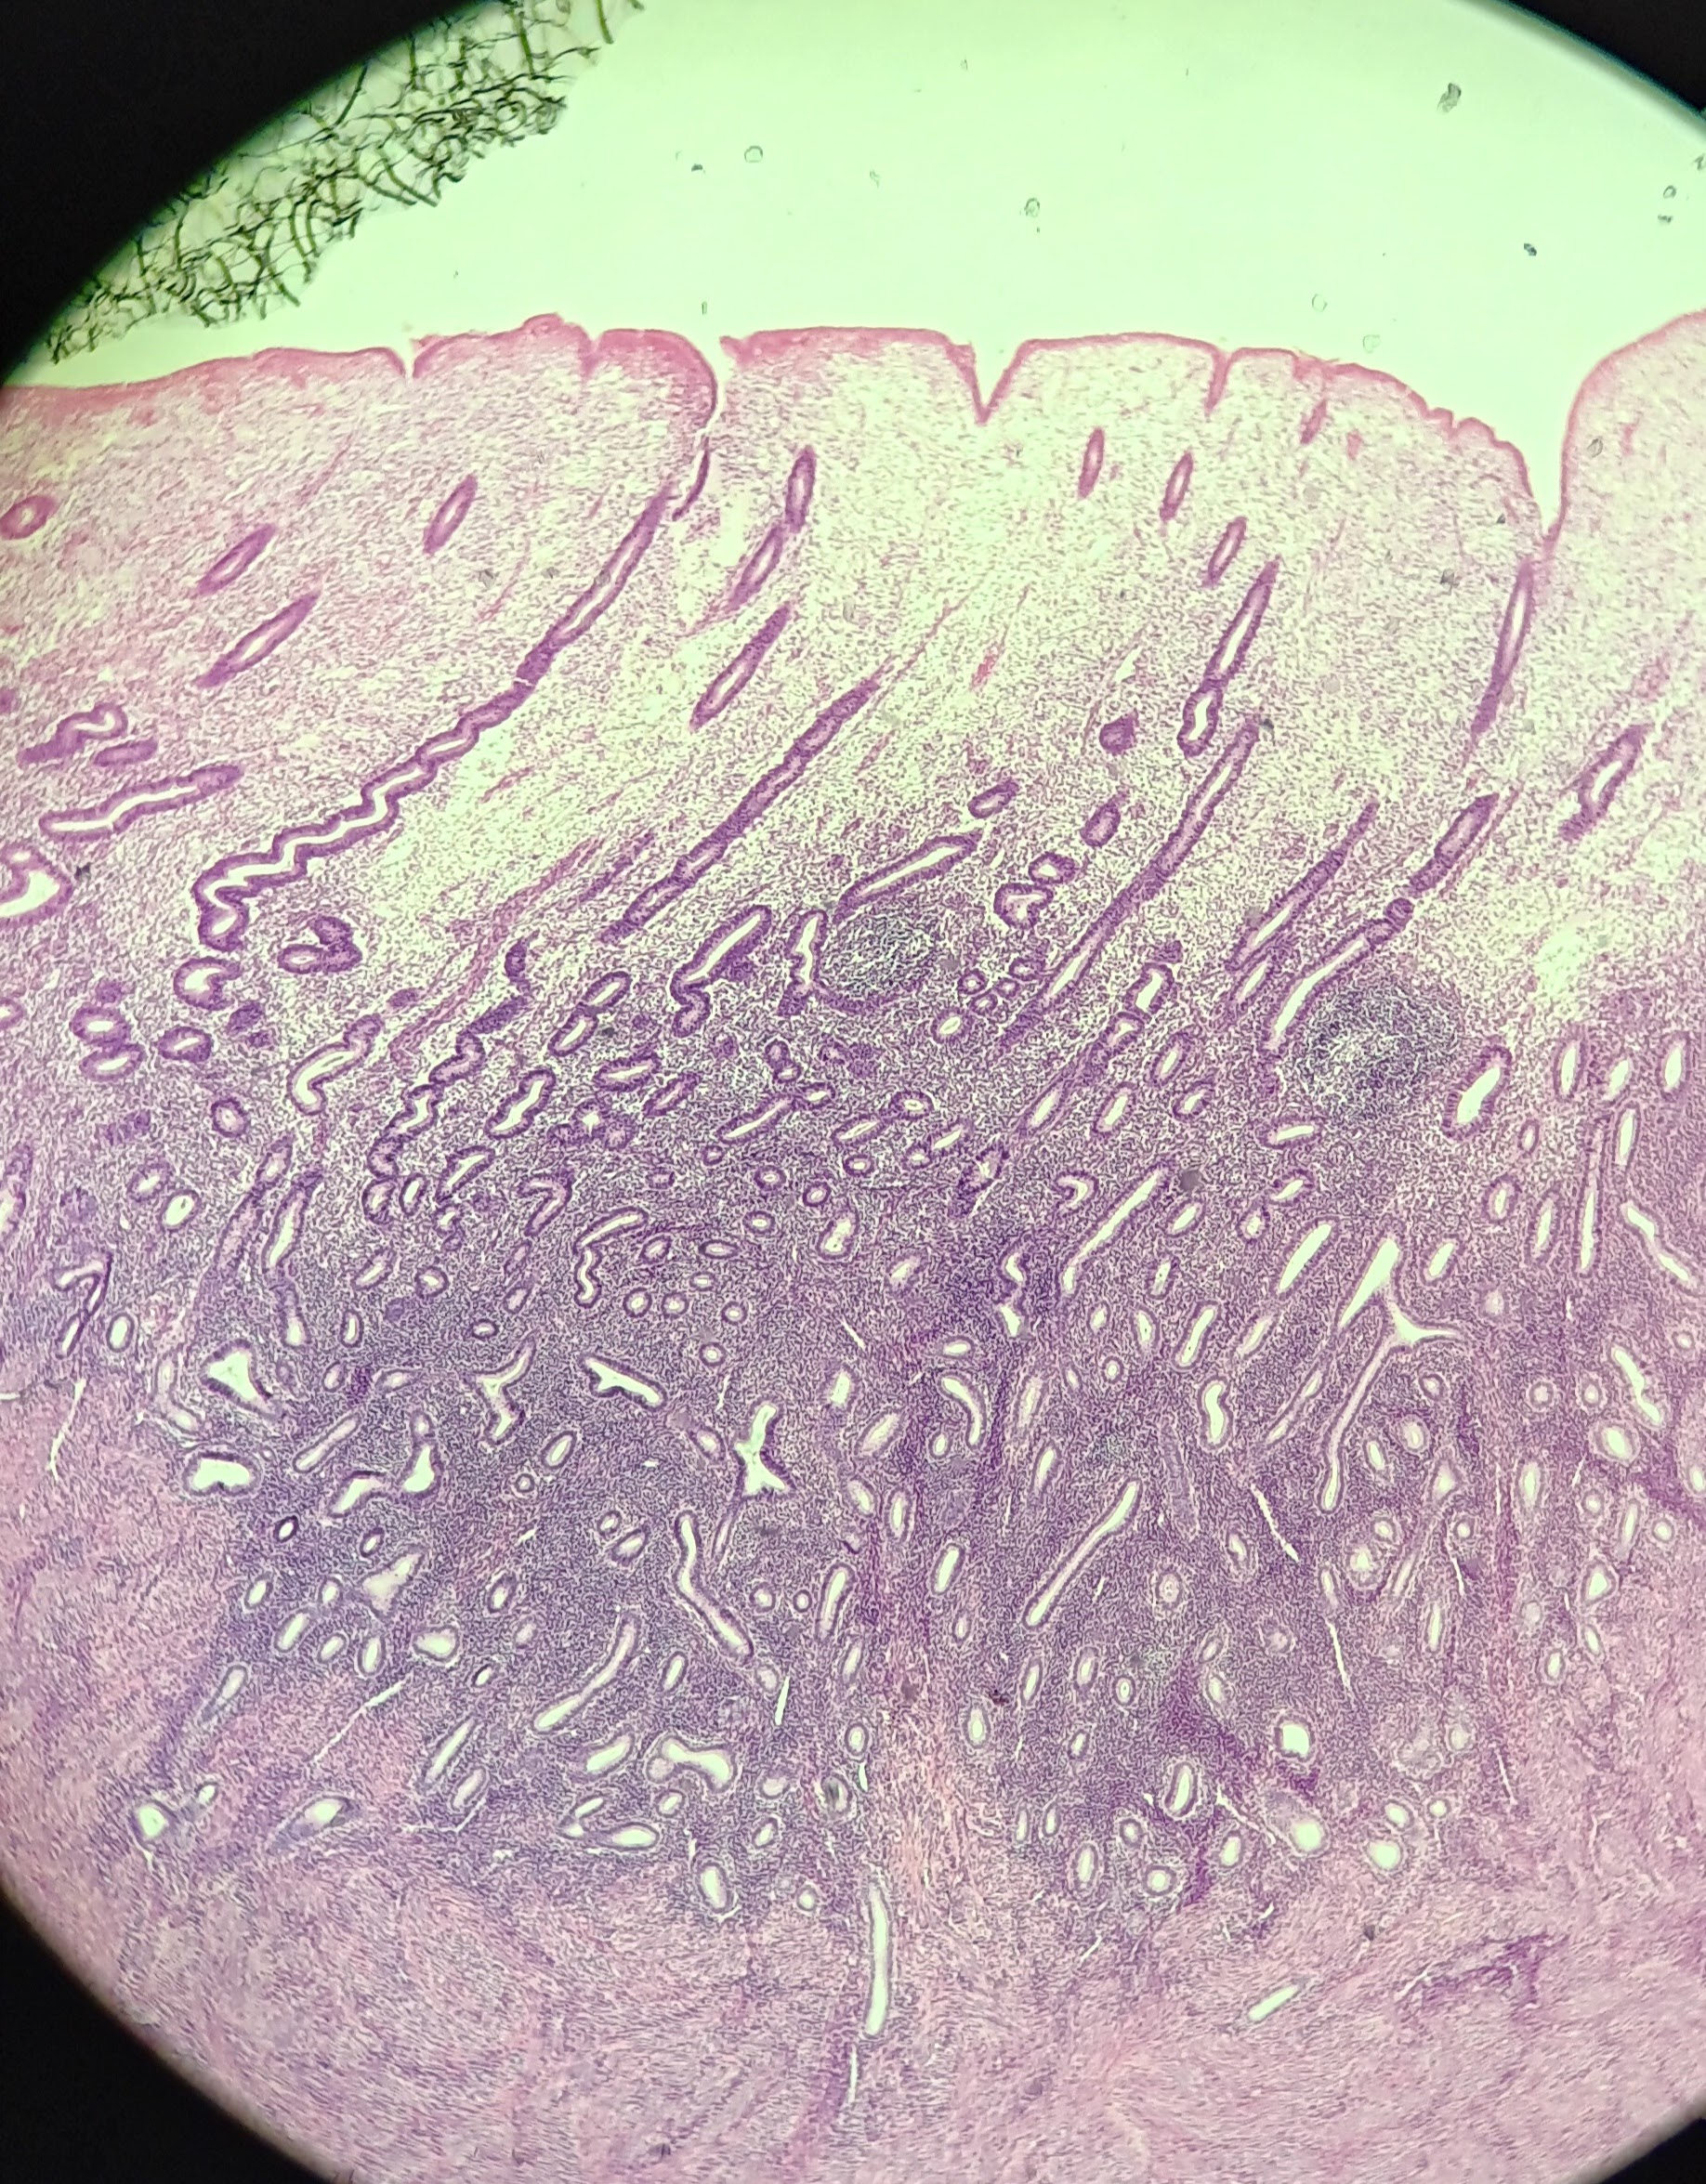

Vagina

Endometrium

Endometrium

Uterine gland